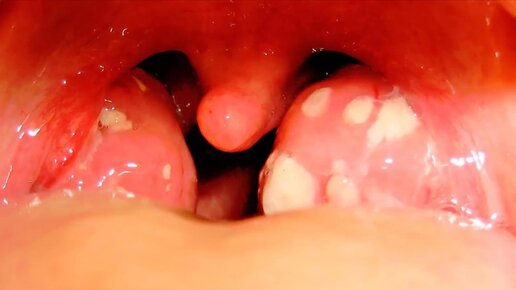

Ангина симптомы у детей - медицинские советы, лечение